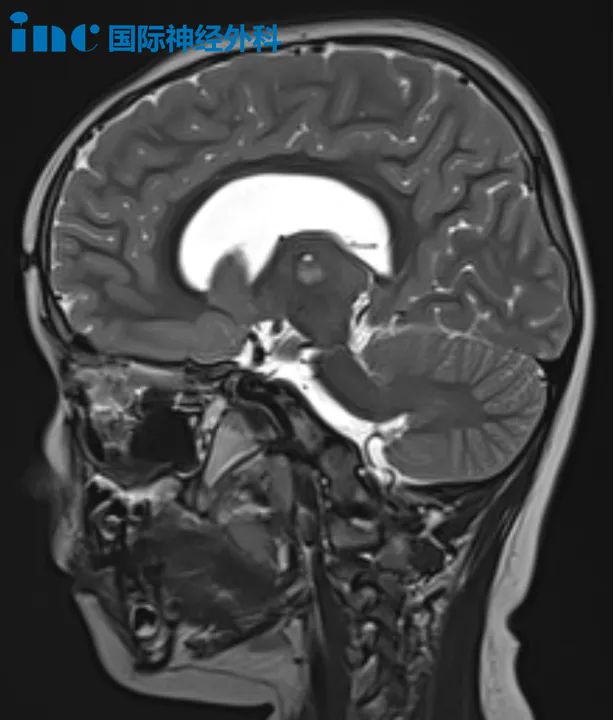

22岁患者小翼确诊神经纤维瘤病I型,近年来因脑部肿瘤囊性成分明显增大,症状持续加重,表现为头晕头痛频发、行走不稳、频繁跌倒。巴特朗菲教授建议立即手术,切除肿瘤实体部分并引流囊液,解除脑干压迫,术后可能无需放化疗。